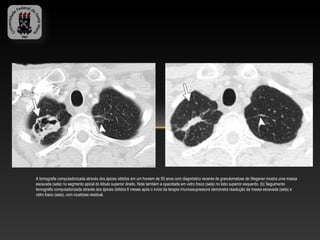

A tomografia computadorizada através dos ápices obtidos em um homem de 50 anos com diagnóstico recente de granulomatose de Wegener mostra uma massa

escavada (seta) no segmento apical do lóbulo superior direito. Note também a opacidade em vidro fosco (seta) no lobo superior esquerdo. (b) Seguimento

tomografia computadorizada através dos ápices obtidos 6 meses após o início da terapia imunossupressora demonstra resolução da massa escavada (seta) e

vidro fosco (seta), com cicatrizes residual.